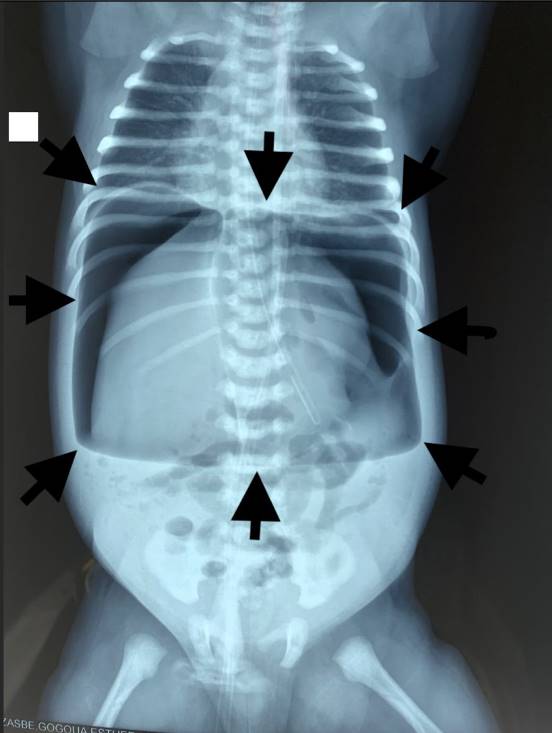

On physical examination she weighed 3200 g, was hypotonic, with signs of dehydration, febrile at 38.7˚C, Silverman score 4/10. The heart rate was 150 c/minute and the peripheral pulses were perceptible with signs of hypovolemia and signs of dehydration. The abdomen was distended, shiny, hypersonous on percussion and silent on auscultation. On rectal examination, the anus was well formed and permeable. Unprepared abdominal x-ray revealed a huge oval radiolucency delineated by the parietal peritoneum of the abdominal wall: American football sign (Figure 1), with the visible falciform ligament outlined by air (Figure 2).

Figure 1. The American football image.

Figure 2. Anteroposterior radiograph of a neonate showing a large radiolucency resembling the shape of an American football. It is demarcated by the parietal peritoneal reflections (arrowheads). The falciform ligament is seen outlined by air (arrows).

The football sign, seen at supine abdominal radiography, refers to a large oval radiolucency that represents a large amount of pneumoperitoneum in the shape of an American football. We presented a case of a newborn who presented a football sign on radiography with no evidence of perforation after laparotomy. Massive idiopathic pneumoperitoneum has been the final diagnostic.